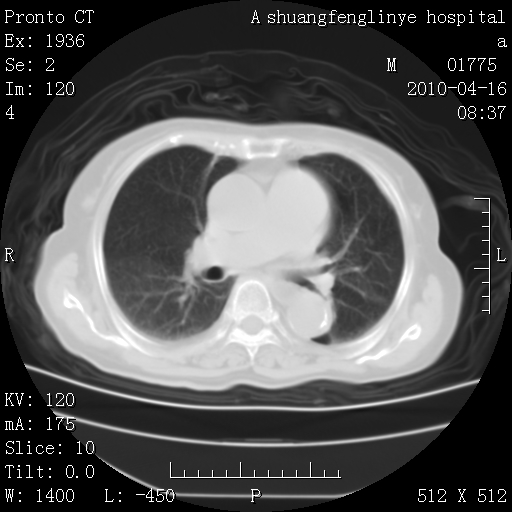

考虑左肺上叶增殖灶、纤维灶。

支持结核

老年肺间质纤维化,肺动脉高压-----肺心病。

慢支肺气肿,左上陈旧性结核,主动脉冠脉钙化

1)左肺上叶结核(纤维、增殖病灶)。2)冠状动脉及主动脉钙化。

1)左肺上叶结核(纤维、增殖病灶)。2)冠状动脉及主动脉钙化。肺动脉高压